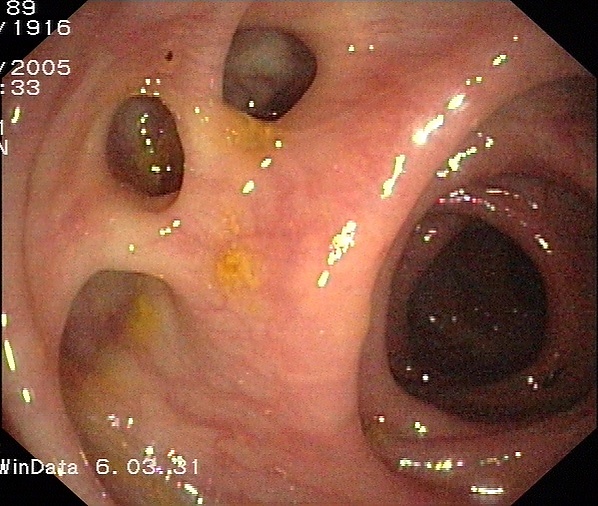

Колоноскопи́я, также фиброколоноскопия или ФКС — медицинский эндоскопический диагностический метод, во время которого врач осматривает и оценивает состояние внутренней поверхности толстой кишки при помощи эндоскопа. Колоноскопия даёт возможность визуально диагностировать такие заболевания, как образование язвы, полипы и др., а также провести биопсию и удалить эти поражения. Колоноскопия позволяет удалять полипы размером от долей миллиметра до 30-40 мм (в зависимости от их строения решение об удалении принимается во время первичного осмотра). Сразу после удаления полипа его можно исследовать в гистологической лаборатории и определить тип его строения. Это поможет спрогнозировать риски развития онкологических заболеваний у пациента в дальнейшем.

Удаление полипов при колоноскопии - важная процедура, позволяющая исключить вероятность развития злокачественного перерождения полипа.

Регулярное проведение колоноскопии с целью профилактики 1 раз в 5 лет лицам старше 40 лет (при отсутствии противопоказаний или специальных показаний) позволяет значительно снизить заболеваемость колоректальным раком (рак толстой кишки).